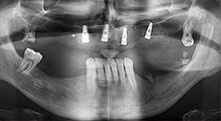

Bratu: Nos gusta utilizar la técnica de sándwich para realizar aumentos en la cara lateral del maxilar inferior. En este procedimiento, se utiliza la sierra piezoquirúrgica para preparar una tapa ósea, mientras que el fragmento crestal se fija con microtornillos. Entre medias, colocamos una combinación de hueso autólogo y material óseo adicional xenógeno. Y con ello obtenemos un rendimiento muy fiable. Asimismo, en los ranurados de la cresta alveolar del maxilar inferior, nunca se puede prescindir de cortes verticales suficientemente dimensionados, pues, de lo contrario, los huesos pueden fracturarse fácilmente.